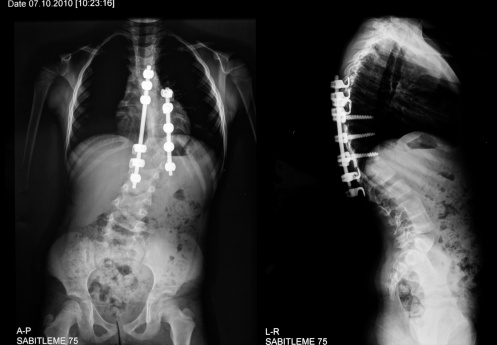

- Spinal fusion surgery where metal rods improve the spine